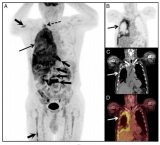

诊断类放射性药品首次通过国谈进入国家医保

12月7日,国家医疗保障局发布《国家基本医疗保险、工伤保险和生育保险药品目录(2025年)》,锝[99mTc]替曲膦注射液正式纳入2025年国家医保目录,成为国内首个通过国谈进入国家医保目录的诊断类放射性药品。此前,东诚药业公告称,公司全资子公司安迪科的锝[99mTc]替曲膦注射液产品被纳入《国家基本医疗保险、生育保险和工伤保险药品目录(2025年)》,这将提高患者对SPECT-MPI检查的可及性,促进冠状动脉疾病诊疗精准化。中华医学会核医学分会前任主... 2025-12-10 放射性药物